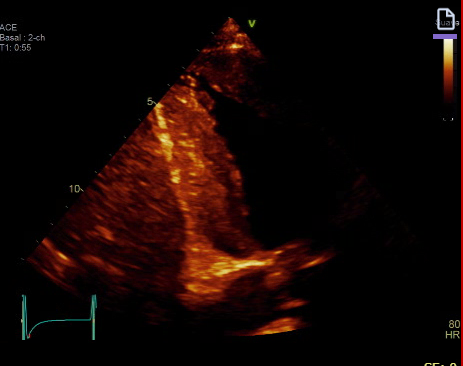

- Ecografía cardíaca: Ventrículo izquierdo con hipertrofia severa de 18-20 mm aproximadamente.

* Imagen 2: 4 cámaras.

* Imagen 3: Corte transversal en el que se objetiva diámetro de ventrículo izquierdo en sístole y diástole.

* Imagen 4: Engrosamiento de pared ventricular izquierda.